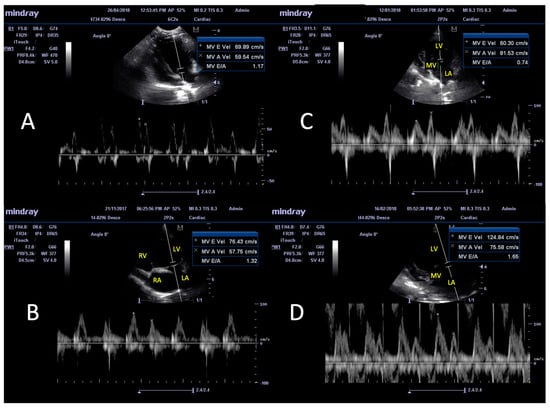

3.4. Pulse Doppler Ultrasonographic Findings

| E/A ratio 1 | PW Doppler | 1.53 ± 0.34 a | 1.24 ± 0.24 | 1.35 ± 0.26 | 1.37 ± 0.34 | 1.41 ± 0.61 | 1.1 ± 0.29 a |

| Parameters | Mode | A (n = 23) | B (n = 6) | C (n = 85) | Reference Range | |||

|---|---|---|---|---|---|---|---|---|

| Increase (%) | Decrease (%) | Increase (%) | Decrease (%) | Increase (%) | Decrease (%) | |||

| IVS, at diastole (IVS-d) | M mode | 4.35 | … | … | … | 8.24 | 1.18 | 0.29–0.59 1 |

| IVS, at systole (IVS-s) | M mode | 13.04 | … | 16.67 | … | 22.35 | 2.35 | 0.43–0.79 1 |

| LVID, at diastole (LVID-d) | M mode | … | 21.74 | … | 16.67 | … | 38.82 | 1.27–1.85 1 |

| LVIDW, at systole (LVID-s) | M mode | … | 21.74 | … | … | … | 42.35 | 0.71–1.26 1 |

| LVPW, at diastole (LVPW-d) | M mode | 13.04 | … | … | … | 10.59 | 1.18 | 0.29–0.60 1 |

| LVPW, at systole (LVPW-s) | M mode | … | … | … | 33.33 | 9.41 | 1.18 | 0.48–0.87 1 |

| Fractional shortening (FS) | M mode | 8.70 | 13.04 | … | 16.67 | 22.35 | 20.00 | 33.6–49.9 2 |

| Ejection fraction (EF) | M mode | 8.70 | 4.35 | … | 16.67 | 22.35 | 12.94 | 58.9–82.9 3 |

| E/A ratio | PW Doppler | 26.09 | 8.70 | 16.67 | … | 11.76 | 3.53 | 0.98–1.7 4 |